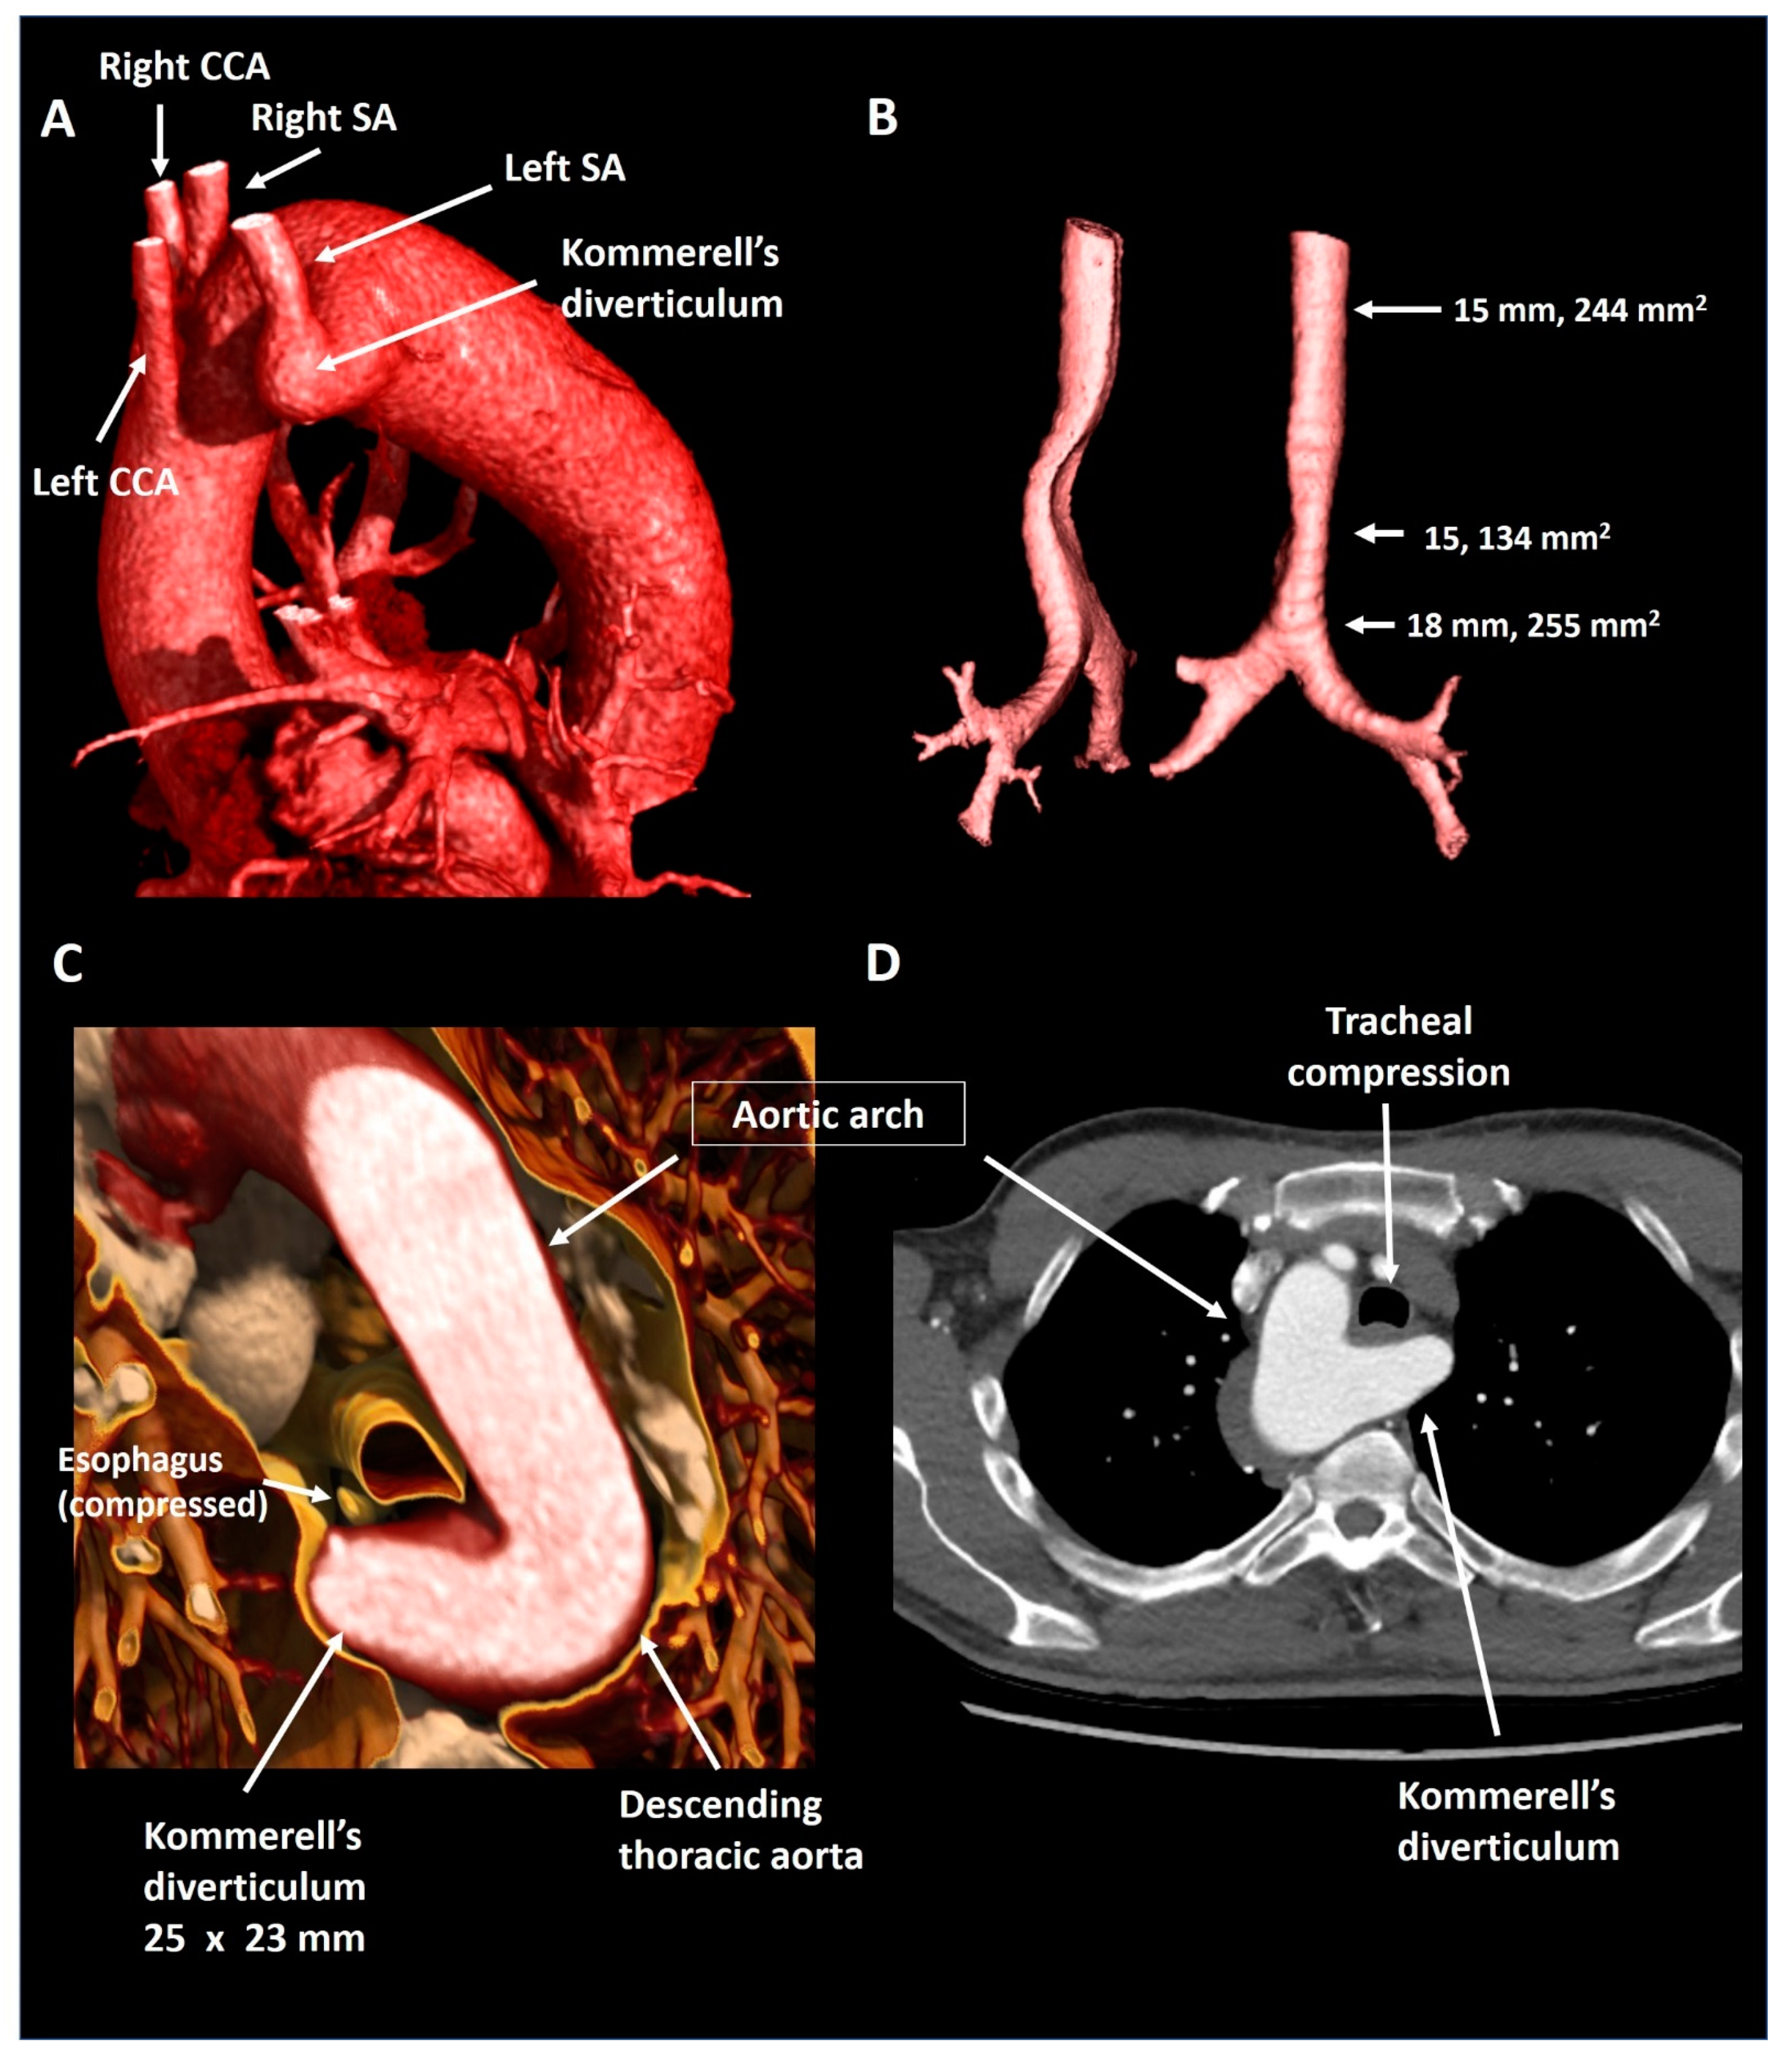

2.4. Patient 4

| Patient 4 | 55 | Male | Right-sided arch, aberrant LSA and KD | Mild tracheal compression | 25 × 23 mm, 575 mm2 | Mild dyspnea, although excellent objective exercise capacity | Structural imaging follow-up |